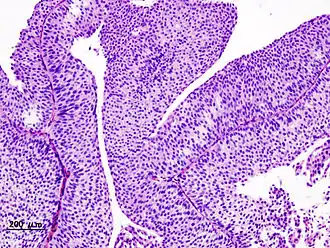

Самой распространённой формой рака мочевого пузыря является переходноклеточный рак (развивающийся из переходного эпителия мочевых путей), более редко встречаются плоскоклеточный рак и аденокарцинома (опухоль, происходящая и построенная из железистого эпителия). Болезнь может проявляться в виде папиллярных разрастаний (нелинейные пристеночные включения) с малигнизацией или солидной, изъязвлённой, инвазирующей опухоли. Различают рак мочевого пузыря in situ, поверхностный рак (Т1-2) и рак, инвазирующий мышечный слой и окружающие ткани (ТЗ-4).